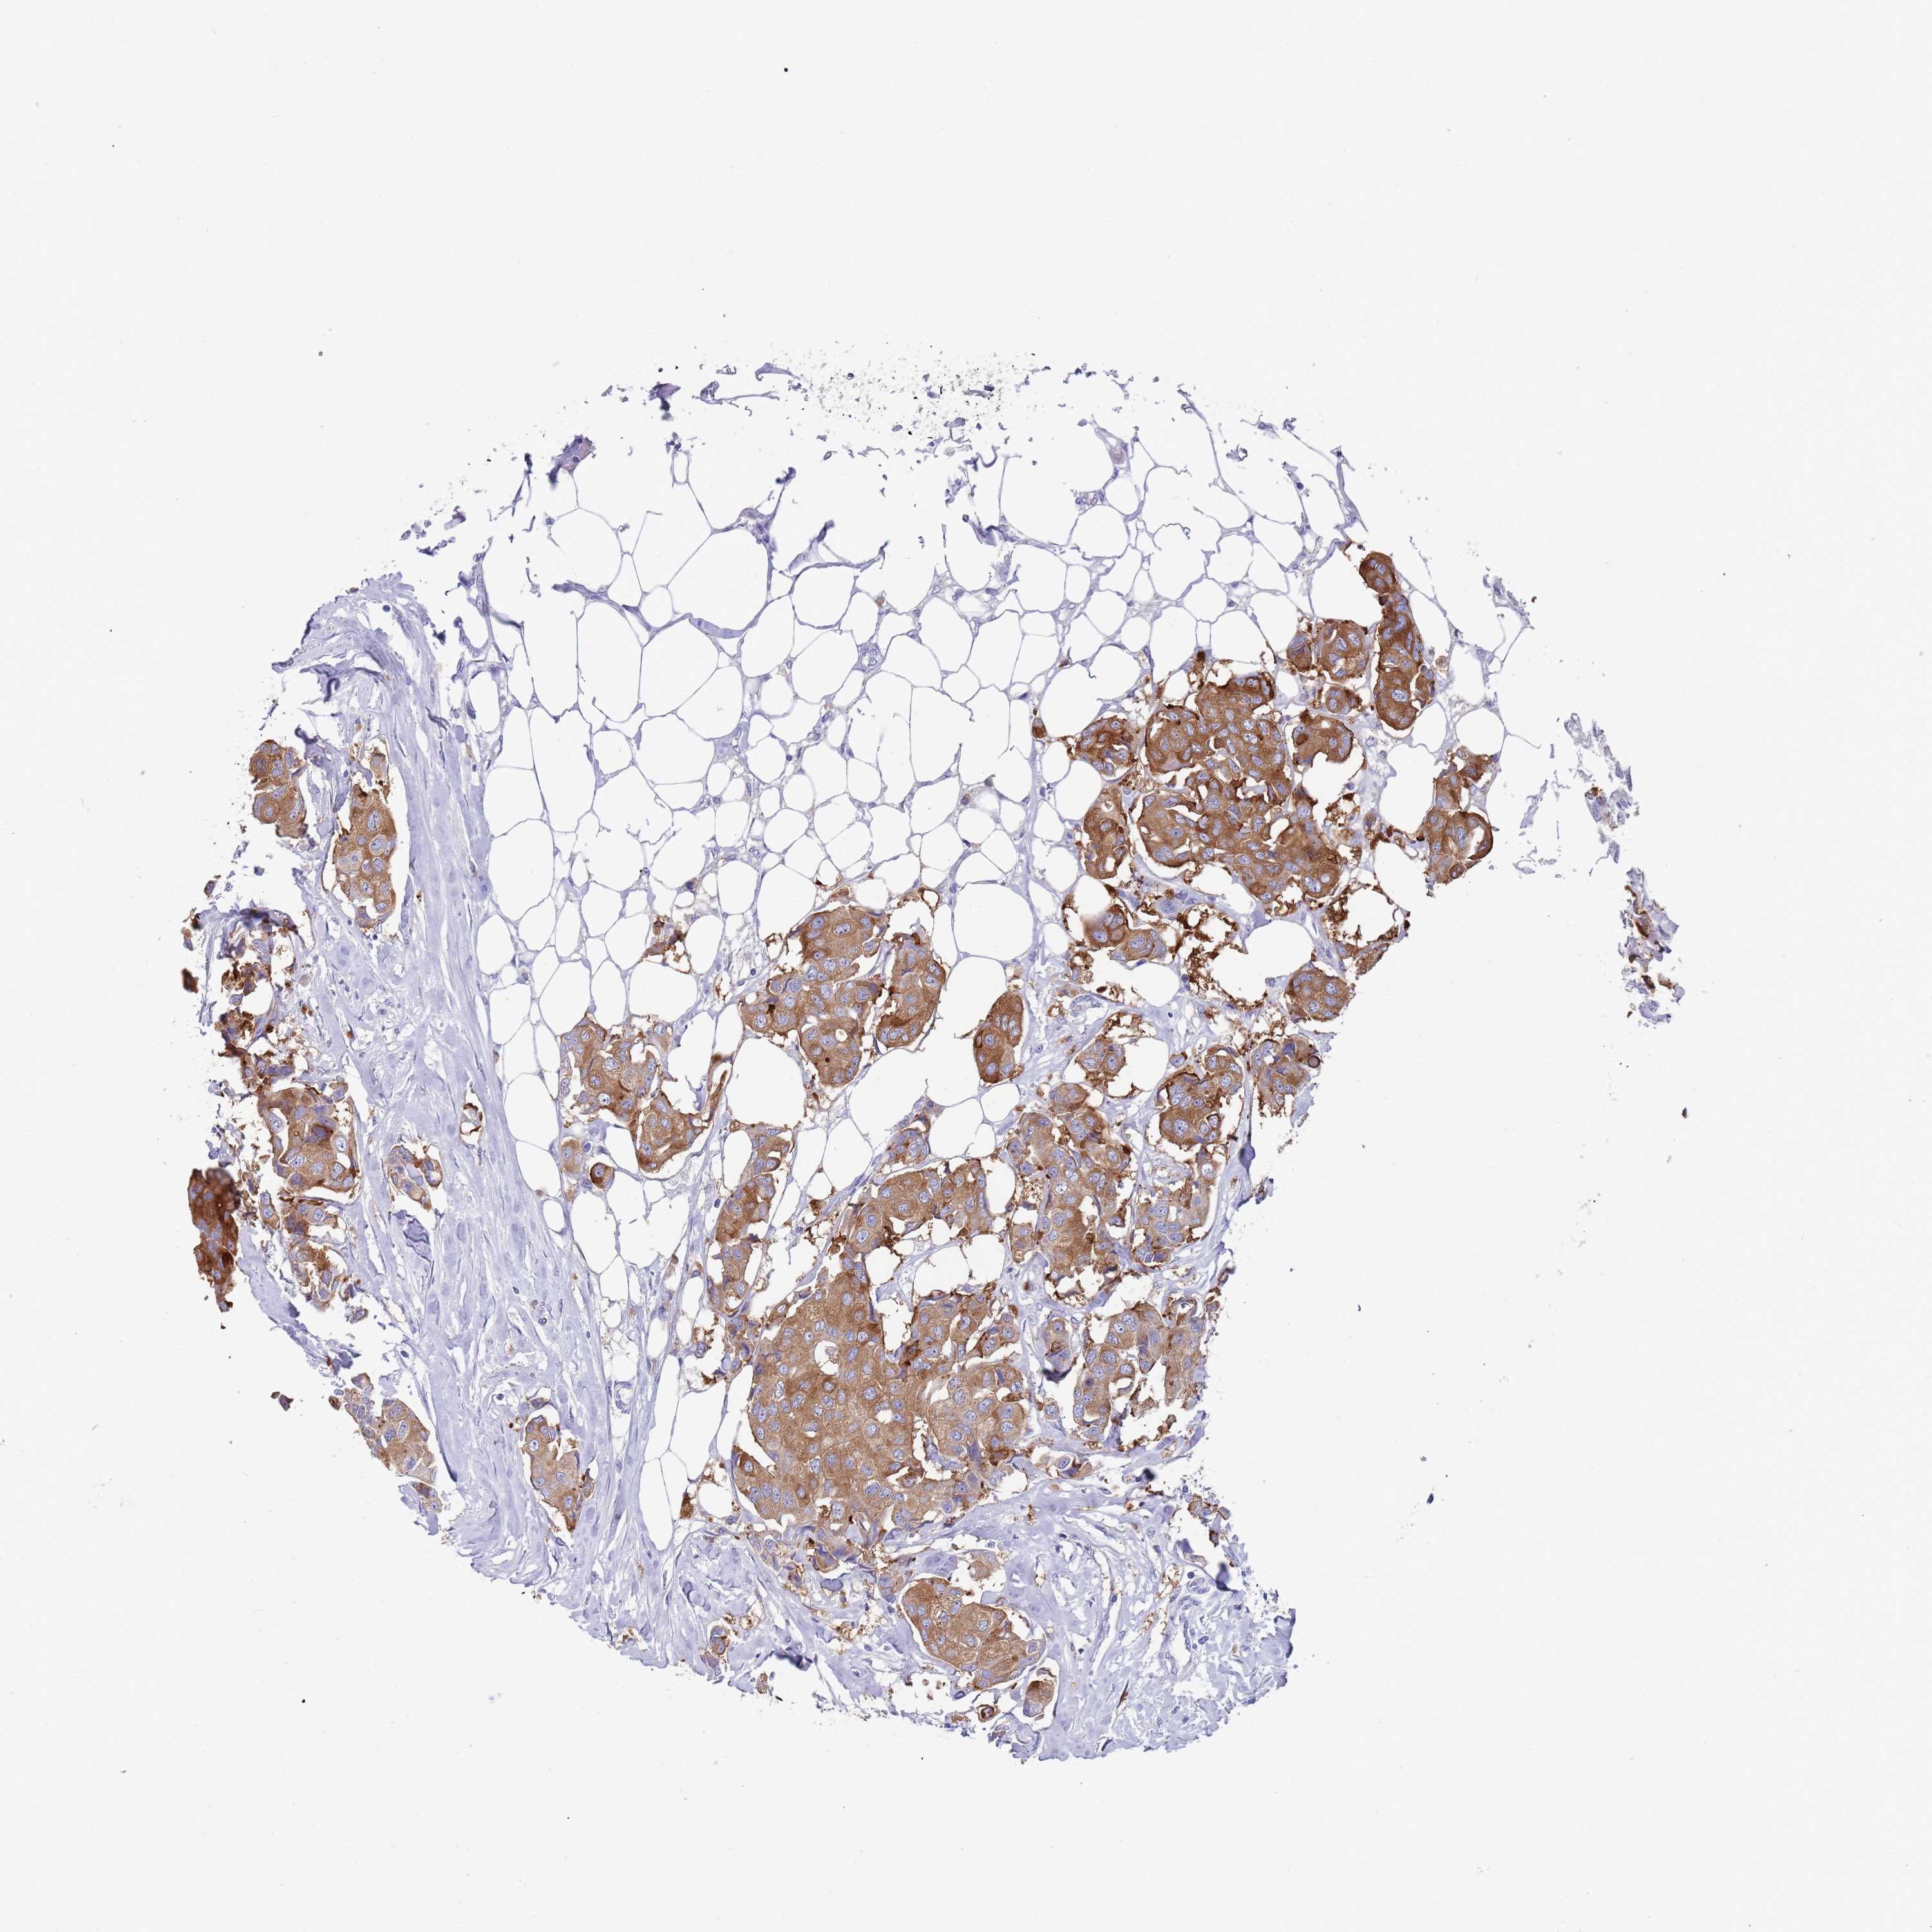

CANCER BREAST CANCER Show tissue menu

BRCA TCGA BRCA VALIDATION PROTEIN EXPRESSION